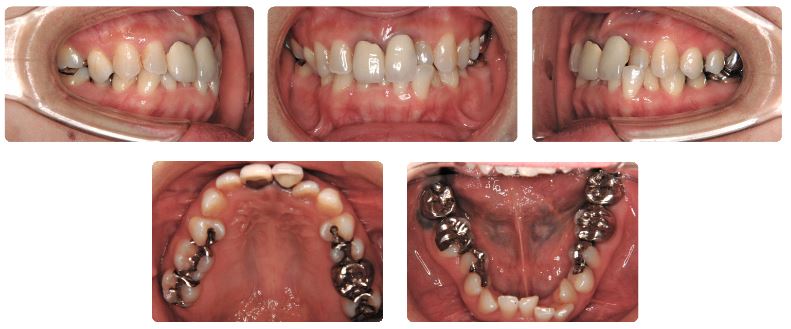

主訴:前歯の歯並びが気になる

初診時年齢:43歳

性別:女性

診断名:叢生

抜歯/非抜歯:非抜歯

装置名:マルチブラケット装置

前歯のセラミックの人工歯がすぐに割れてしまうとのことで前歯の歯並びを治したいとのことで来院されました。

上下顎の前歯と臼歯の噛み合わせがとても深い状態です。

また補綴などの治療部位がとても多く、特に上あご前歯は要再治療の状態です。